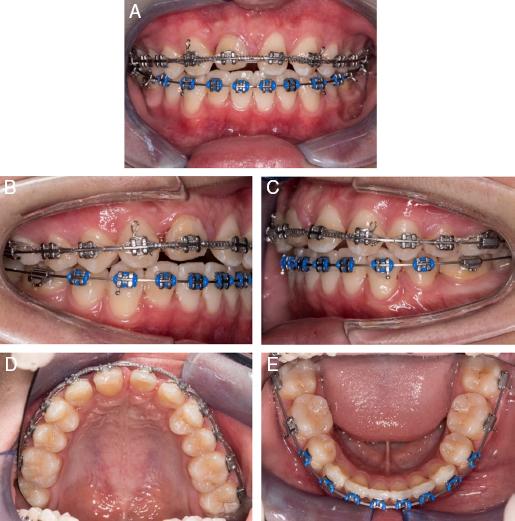

Orthodontic treatment began 6 months after the transplantation. Upper and lower pre-adjusted fixed appliances (MBT prescription, 0.022˝ × 0.028˝ slot; 3MTM Unitek Gemini) were placed. Once in 0.019˝ × 0.025˝ stainless steel wires, space closure was performed to mesialise the transplanted tooth towards the midline. Full-time Class II (3.5 oz, ¼˝) elastics were bilaterally added to support overjet reduction. Nickel-titanium coil springs were placed between #13 and #23 to prepare spaces for composite build-up (Figure 4A-E). The transplanted tooth was reshaped with selective enamel grinding on the palatal cusp to avoid heavy occlusal forces. Finishing step bends were placed to idealise the gingival margins of the transplanted teeth and increase palatal root torque on the upper incisors. The total orthodontic treatment time was 29 months. Following removal of the orthodontic appliances, the prosthodontist was able to carry out composite resin build-ups on #13 – #23. The patient was fitted with an upper fixed bonded retainer and asked to wear upper and lower vacuum-formed retainers on a night-time basis (Figure 5A-G).

(A–E) Midtreatment intra-oral photographs.